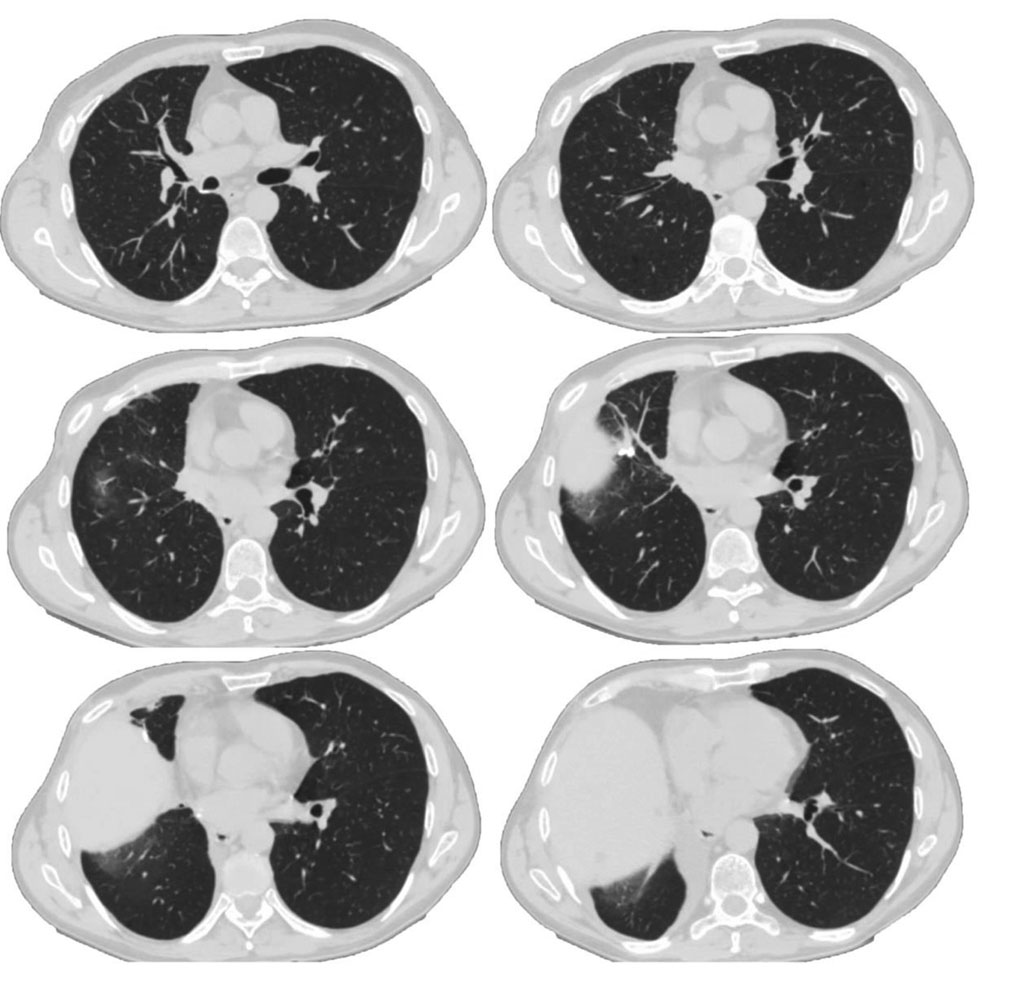

В течение недели после выписки, находясь на амбулаторном лечении по месту жительства, стал отмечать нарастание одышки, усиление продуктивного кашля с отхождением мокроты гнойного характера, снижение толерантности к физическим нагрузкам. В связи с этим вновь обратился за медицинской помощью и был госпитализирован в клинику терапии усовершенствования врачей Военно-медицинской академии им. С.М. Кирова. При поступлении в отделение скорой медицинской помощи по сito! был выполнен лабораторный контроль: Д-димер 1560 нг/мл, СОЭ 61 мм/ч. На этом фоне предъявлял жалобы на общую слабость, одышку смешанного характера при минимальной физической нагрузке и в покое, кашель с отхождением незначительного количества гнойной мокроты. При объективном осмотре обращало на себя внимание снижение сатурации 85–86% при дыхании атмосферным воздухом. Данные СКТ ОГК при поступлении на реабилитационное лечение представлены на рисунке 3. Определялось расширение корня правого легкого с наличием перибронхиального уплотнения на уровне оперативного вмешательства; полисегментарно в обоих легких определялись субплевральные и перибронхиальные участки уплотнения легочной ткани по типу «матового стекла», сливающиеся между собой, в сочетании с ретикулярными изменениями в виде утолщения внутридольковых и междольковых перегородок; отмечалась эмфизематозная перестройка легочной ткани за счет наличия участков центрилобулярной и парасептальной эмфиземы; в S10 левого легкого выявлены кальцинаты диаметром до 0,3 см; в S5 левого легкого определялся дисковидный ателектаз; в базальных отделах обоих легких прослеживались плевродиафрагмальные спайки; средостение смещено вправо, не расширено, образований в нем не выявлено, лимфоаденопатии нет; стенки сегментарных и субсегментарных бронхов уплотнены, не расширены.

Рис. 3. Спиральная компьютерная томография органов грудной клетки пациента В. при поступлении на реабилитационное лечение

Fig. 3. Spiral computed tomography of patient B’s chest organs upon admission to rehabilitation treatment